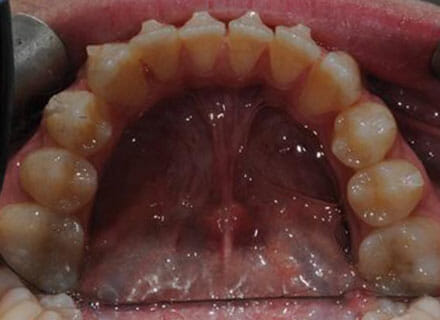

This patient came to us because she hated her smile: it was too narrow, the upper front teeth were all crowded into each other and twisted. She couldn’t eat a sandwich properly with the front teeth because of the gap – the open bite. We were able to expand both jaws to make space to align all the teeth without having to extract – in about 18 months using clear brackets.